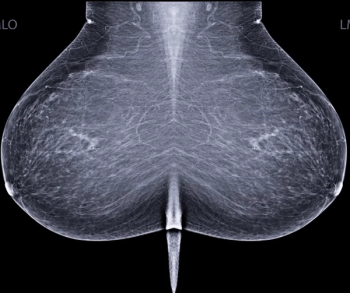

In separate test sets of Israeli women and United States women who had either ductal carcinoma in situ or invasive breast cancer, emerging artificial intelligence (AI) algorithms achieved an area under the curve (AOC) of 88 percent and 80 percent, respectively, for malignancy detection.